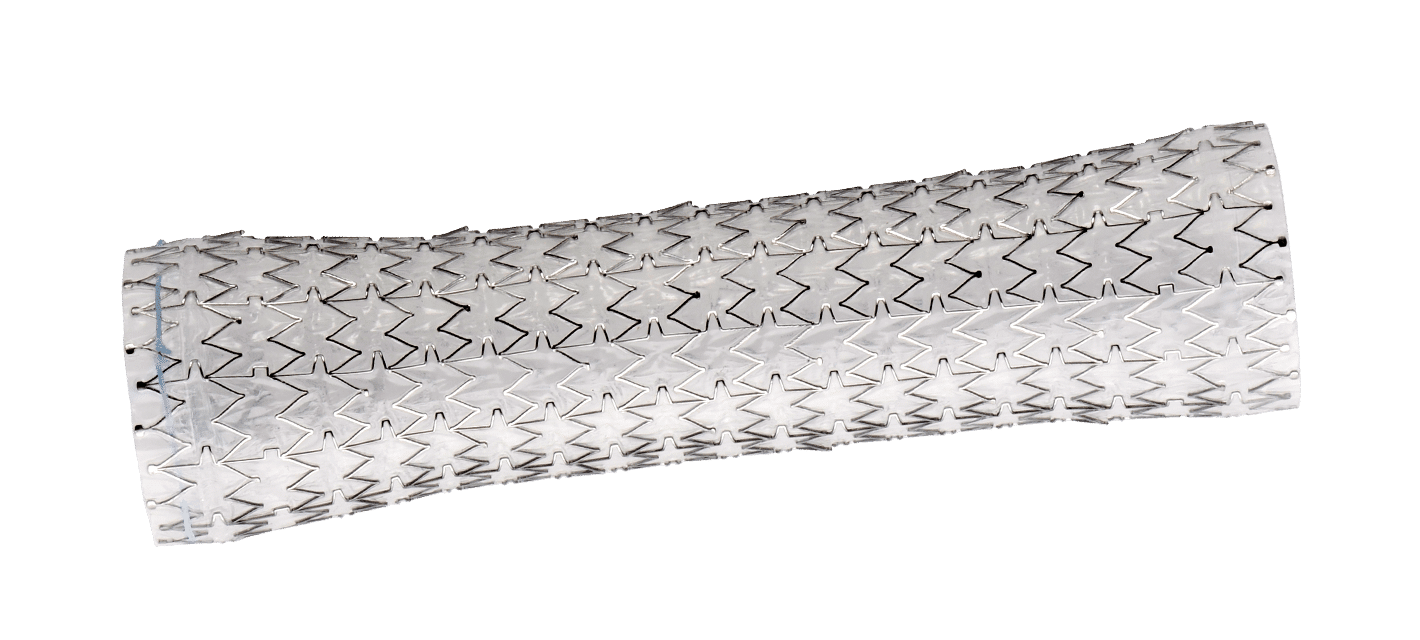

AORTIC ANEURYSM

The aorta runs from the heart through the center of the chest and abdomen. It’s the main blood vessel that brings blood to the abdomen, pelvis, and legs. An abdominal aortic aneurysm (AAA) is a life-threatening condition that occurs when the vessel enlarges, putting it at risk of bursting. Men are 4-15 times more likely to develop an AAA than women

Learn more about AAA. To learn more about our packs, wires, and other cardiac products, please visit our Merit Vascular page.

MERIT PRODUCTS